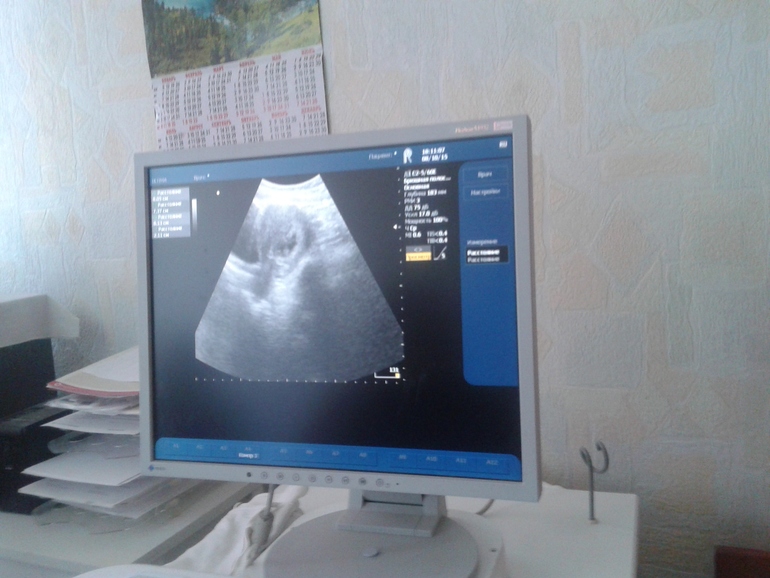

новая узистка говорит, что предыдущей надо оторвать уши )ибо сердечко бьётся превосходно )9акушерских недель это хммм )